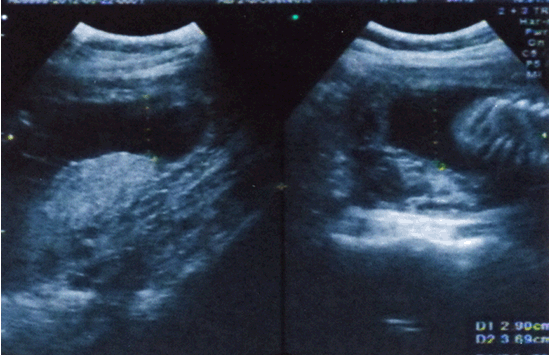

Hình 3. Chỉ số ối ổn định trên 7-8cm trên những lần kiểm tra siêu âm sau truyền ối